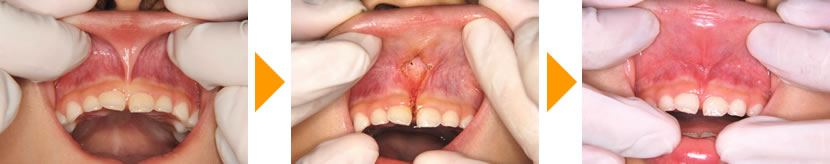

6歳女児(上唇小帯付着異常)

上唇を前に引っ張ると上の写真のようなスジがあり、上唇小帯(じょうしんしょうたい)と呼ばれております。主に上の前歯の間が大きく離れている場合などに切除を検討します。 当クリニックでは、主に学童期のお子さまを中心にメスを使わず、安全にしかも出血も非常に少ないレーザー(Nd‐YAGレーザー)を用いて切除します。切除部を縫合する必要もなく、手術後の飲食も問題なく行えます。 |